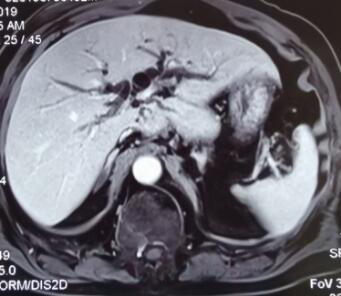

如下图所示:MRI显示:左1图显示肝内胆管扩张,中图MRCP显示:胆总管中下段梗阻,呈截断状,右图显示PTCD引流管置入后造影显示:肝内胆管扩张,胆总管中下段梗阻。